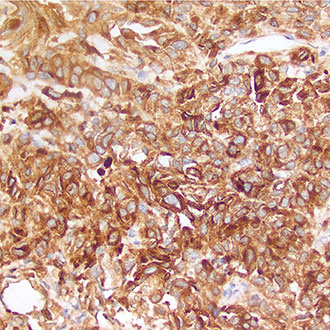

IHC

免疫组织化学(IHC)